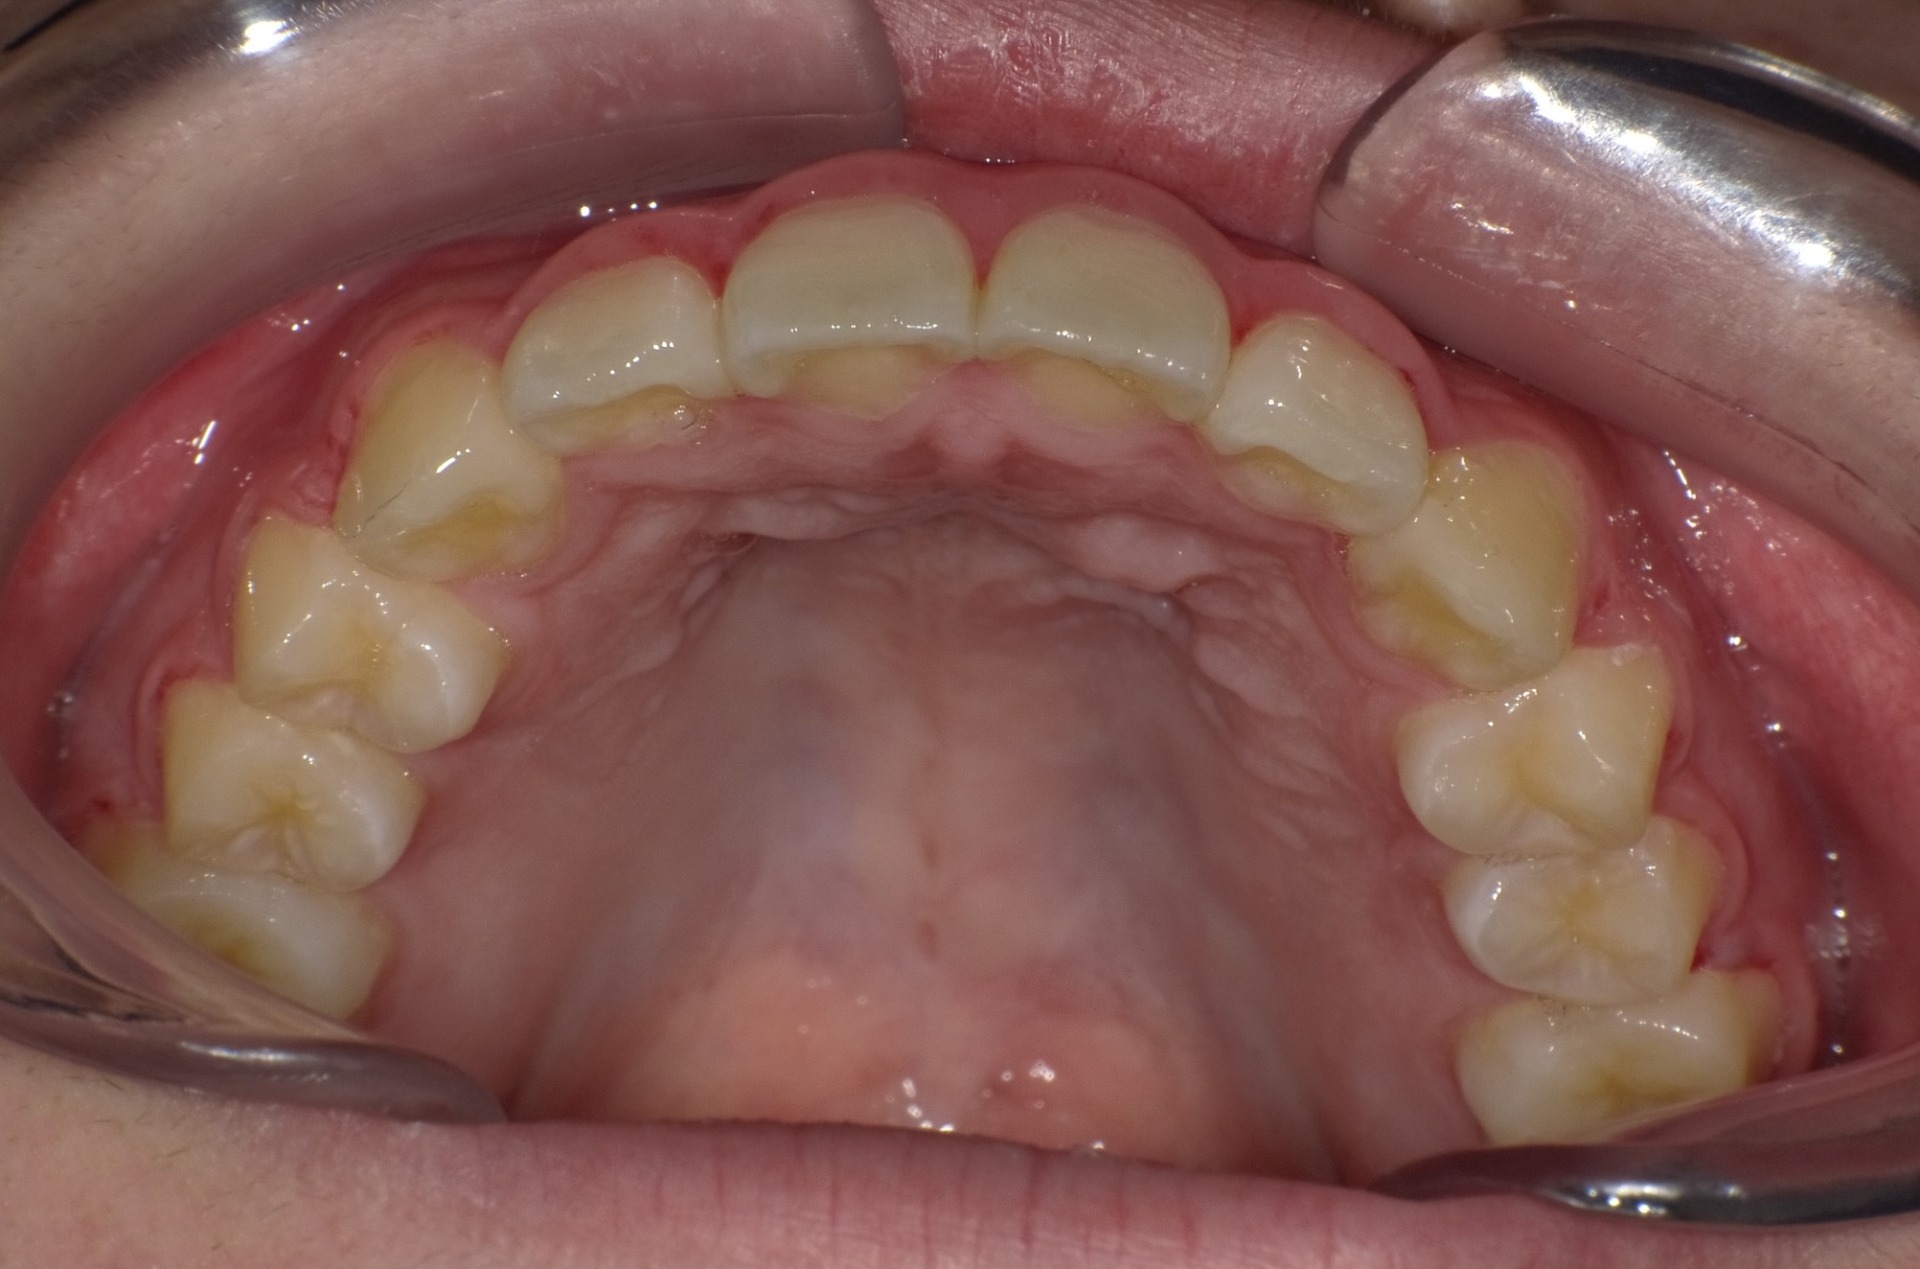

矯正後

| 症状 | 上顎前突 |

| 通院目的 | 永久歯を抜かずに歯並びを治したい。 |

| 処置内容 | バイトブロック・プレート拡大処置・ディスタライザー・インビザライン・オーソテイン・マルチブラケット装置・プリフィニッシャー |

| デメリット・院長コメント | 永久歯を抜かない治療のデメリットは、治療期間が長いことです。 ただし、その後の人生の長さを考えると、健全な小臼歯を2本または4本抜歯の矯正治療よりも、はるかにメリットがあるといえます。 また、アーチが小さくならないので、舌が後ろに押し込まれないためいびき防止につながり睡眠の質の向上にもつながります。 |